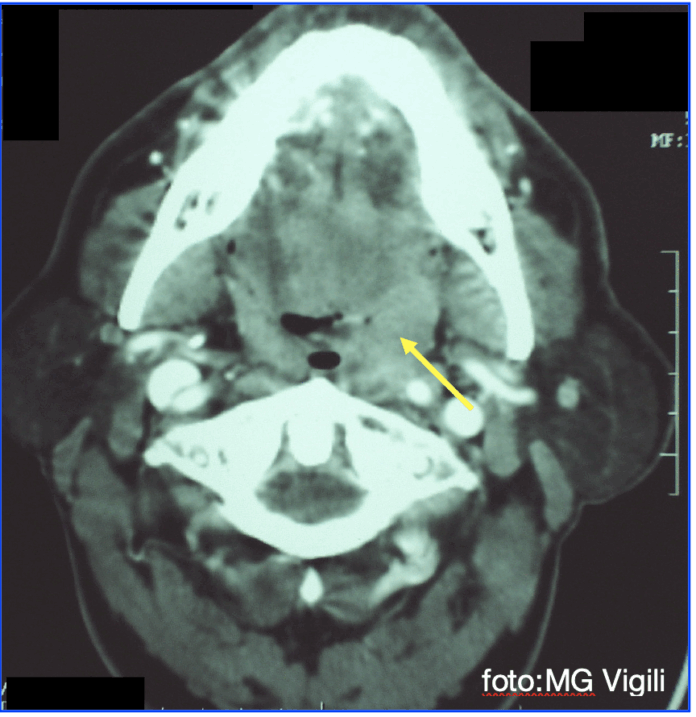

Metastasi linfonodali controlaterali nei carcinomi squamosi della tonsilla. Uno studio di review della Loma Linda University Health, Loma Linda, California, U.S.A ha riscontrato che la prevalenza globale di metastasi linfonodali controlaterali nei Carcinomi squamosi della Tonsilla è del 10%, suddivisa fra 8% nei T1/T2 e 19% nei cT3/T4.

In caso di collo NO l’incidenza è dell’1%, che sale invece al 12% nei casi N+.

La sede più frequente delle metastasi è il II livello (81%) e III livello (19%). Nessuna metastasi era presente al I livello.

I risultati di questo studio suggeriscono di proporre uno svuotamento Selettivo controlaterale (livelli II-IV) nei casi T3/T4 soprattutto se vi sono linfonodi omolaterali sospetti. Nei casi T1/T2 o N0 la probabilità di avere metastasi controlaterali è < 10% ed è quindi opportuna una corretta informazione e discussione con il paziente sui rischi/benefici della procedura. Rimangono in gioco la biopsia del Linfonoso Sentinella o mantenere una politica di wait and see stretta.